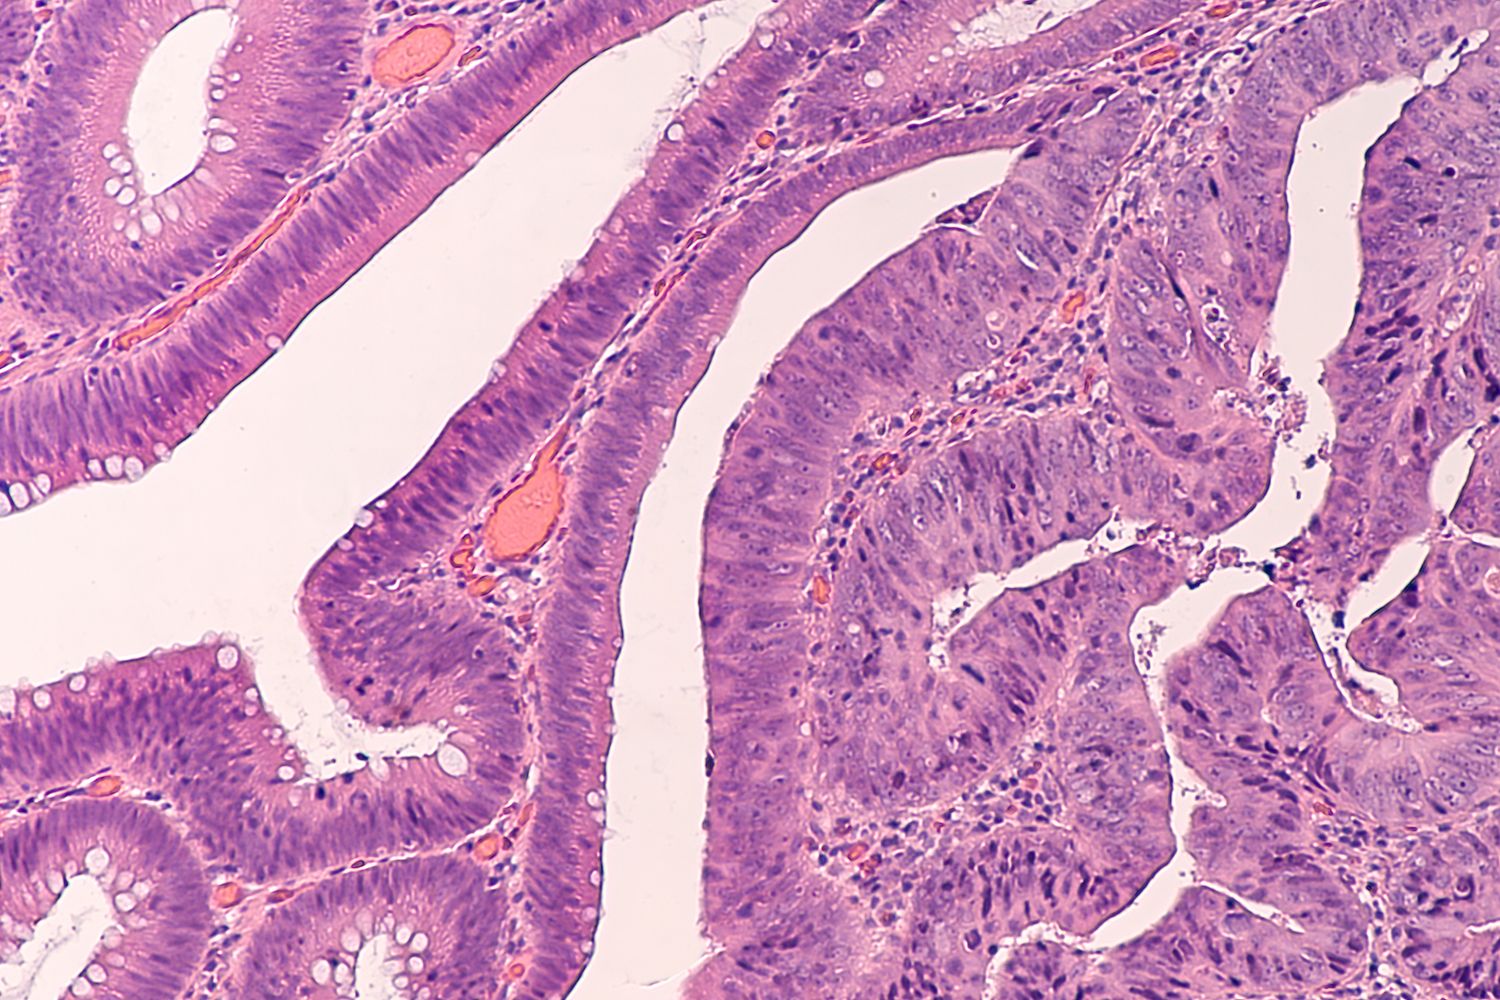

Колоректальный рак чаще всего развивается из полипа. Это образование можно заметить на колоноскопии. Чтобы превратиться в рак, полипу обычно нужно около 10 лет. Если полип удалить, то это предотвратит развитие рака. Для регулярных проверок также используют тест на скрытую кровь в кале. Кровь может появиться в кале из-за полипов или непосредственно рака кишечника. При этом невооруженным глазом ее не заметишь.